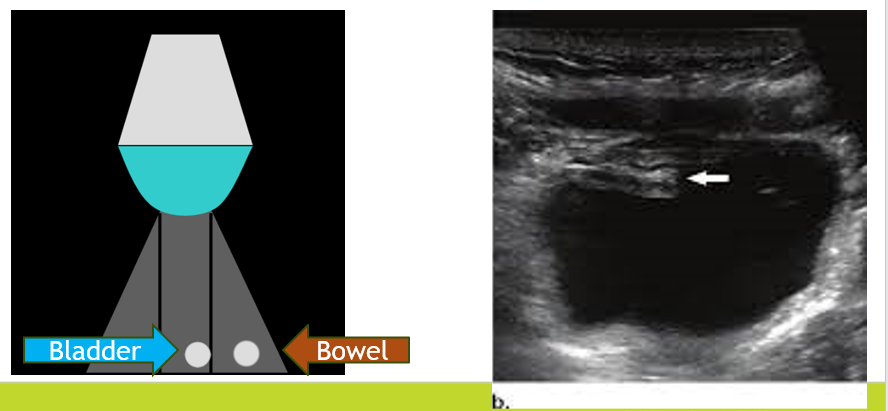

Slice Thickness Artifact

Similar to the beam width artifact but occurs due to the thickness (elevational plane) of the beam.

Often seen within anechoic structures at depth when adjacent bowel and bladder are contained within the same “slice thickness.”